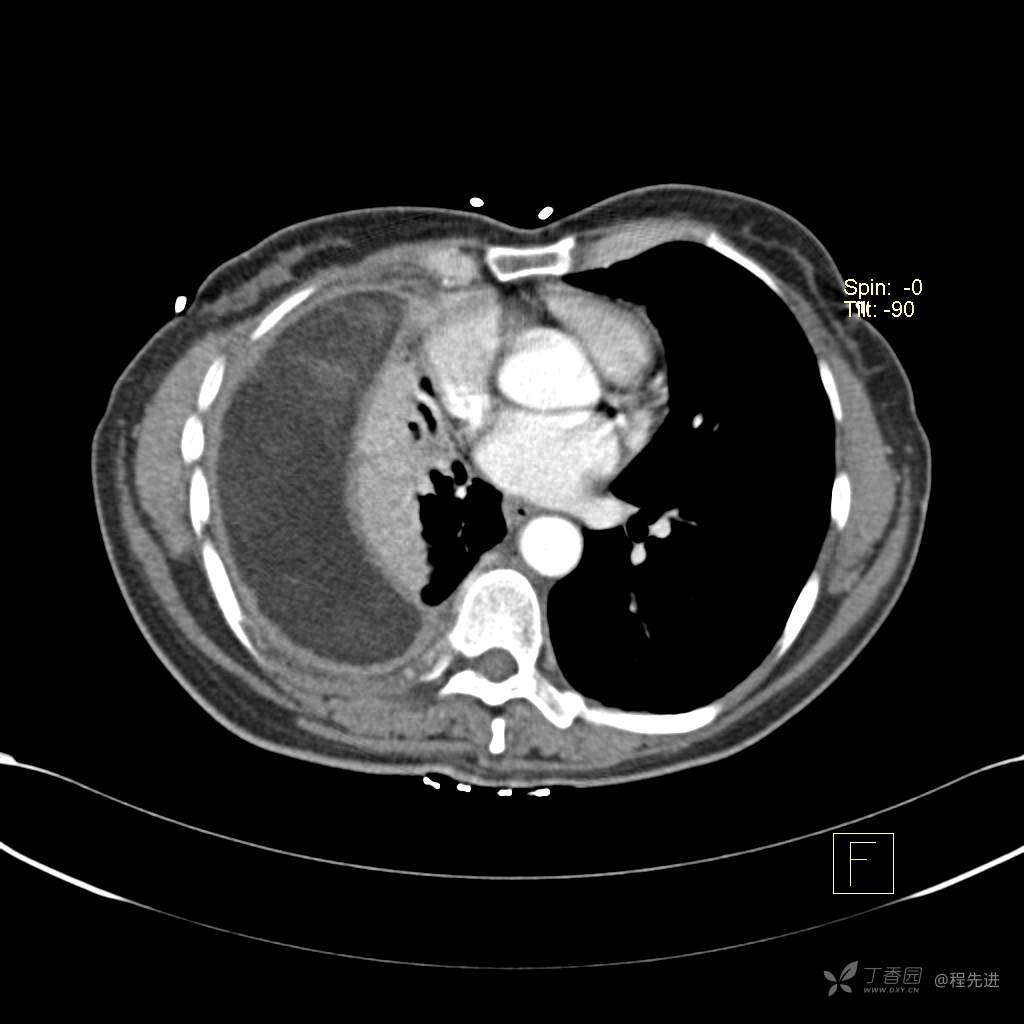

患者性别:女

患者年龄:51岁

简要病史:胸闷半年